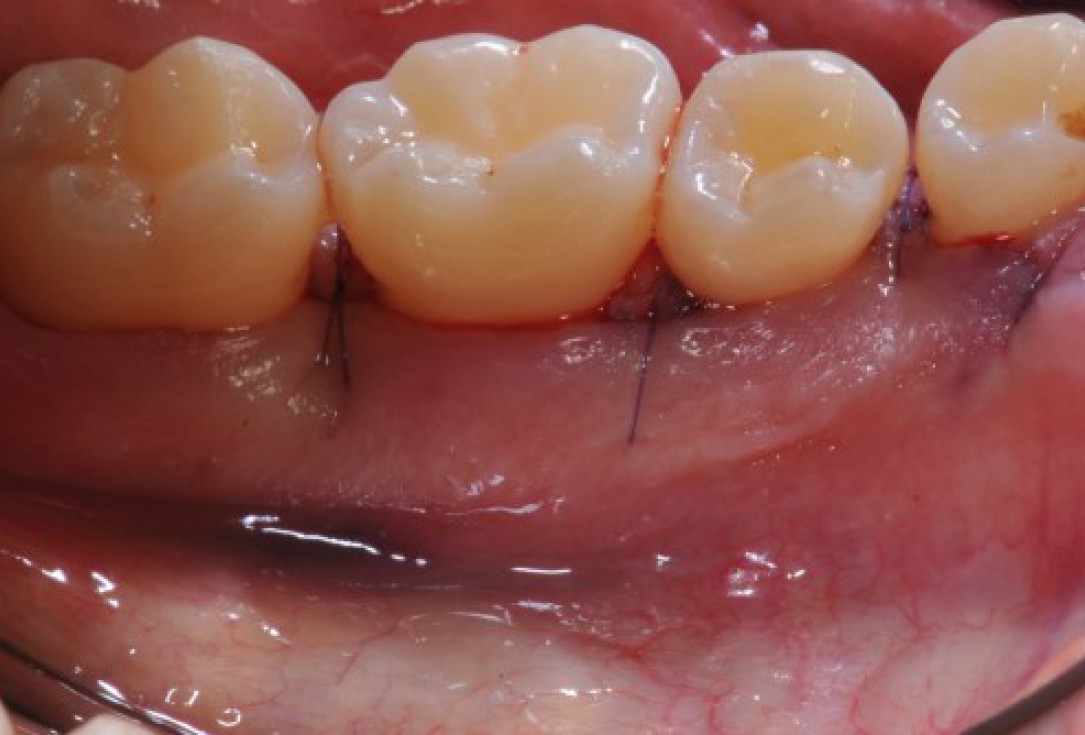

Radiographic view before periodontal regenerative therapy with Straumann® Emdogain®. A deep intrabony defect appeared mesially and distally on the left mandibular first premolar. Pre-surgical probing measured 8 mm. The defect morphology presented as well-contained.